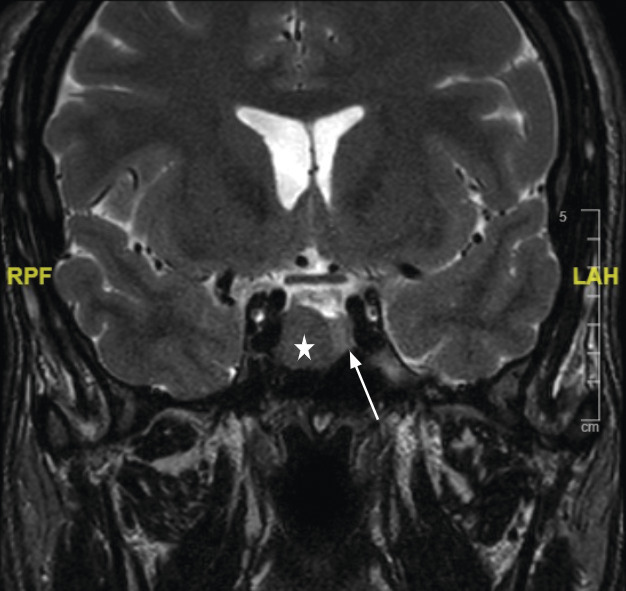

La réalisation d’une IRM hypophysaire permet de visualiser la tumeur (fig. 3, 4 et 5), d’évaluer sa taille et son éventuelle extension aux structures adjacentes.